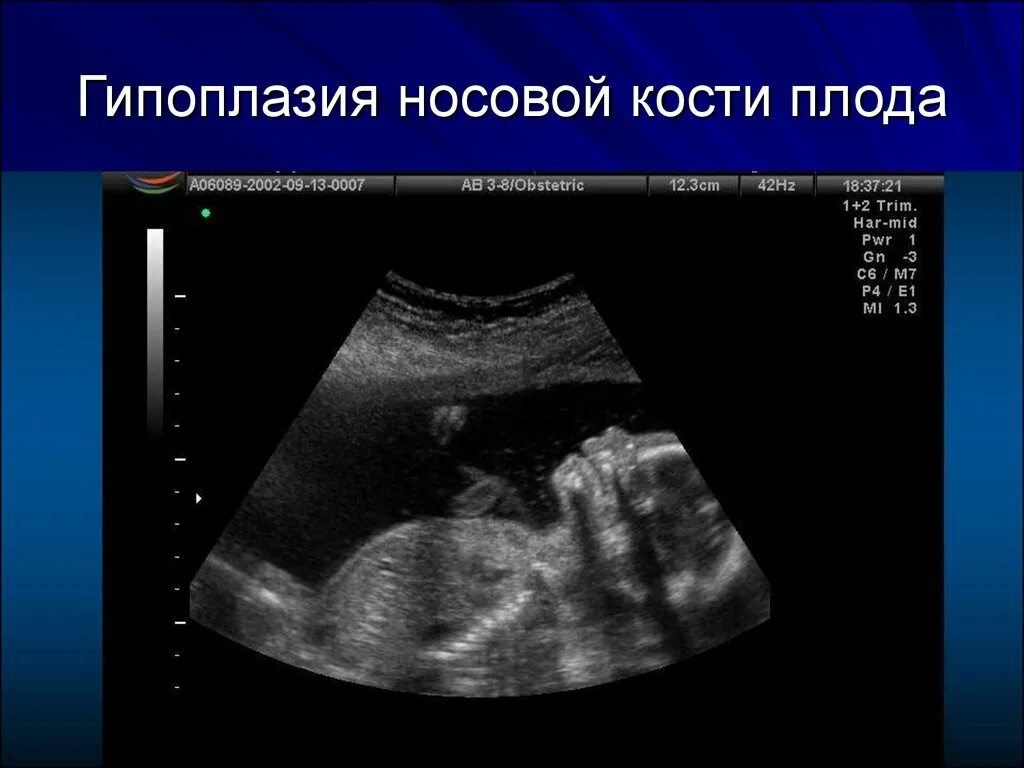

Узи аномалий